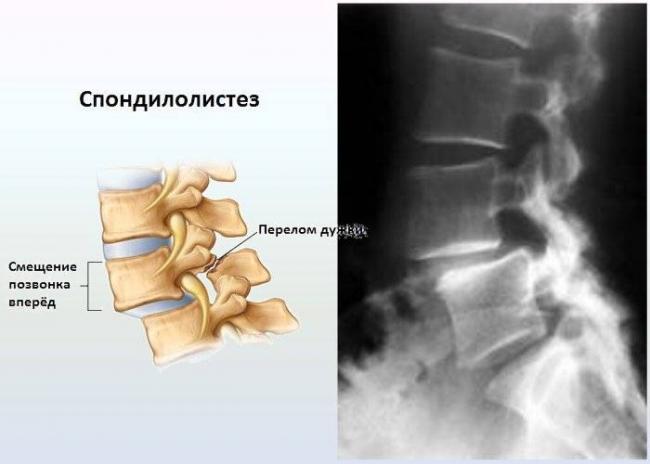

Подтвердить или опровергнуть диагноз позволяет рентген. Он определяет стадию развития заболевания и причину его возникновения. Более информативными методиками считается МРТ или КТ, но их назначают в отдельных случаях для получения развернутой картины состояния пациента.

Рентгеновский снимок является надежным способом обнаружить патологию

Спондилолистез, характеризующийся смещением позвонков в пояснично-крестцовом отделе, вызывает у врачей значительное беспокойство. Основные симптомы, на которые обращают внимание специалисты, включают боль в пояснице, которая может иррадиировать в ноги, а также ограничение подвижности. Пациенты часто жалуются на чувство усталости в спине и мышечную слабость. Врачам важно учитывать, что симптомы могут варьироваться в зависимости от степени смещения и наличия сопутствующих заболеваний. При отсутствии своевременного лечения спондилолистез может привести к серьезным осложнениям, таким как хроническая боль и нарушение функции нервов. Поэтому ранняя диагностика и комплексный подход к терапии играют ключевую роль в успешном восстановлении пациентов.